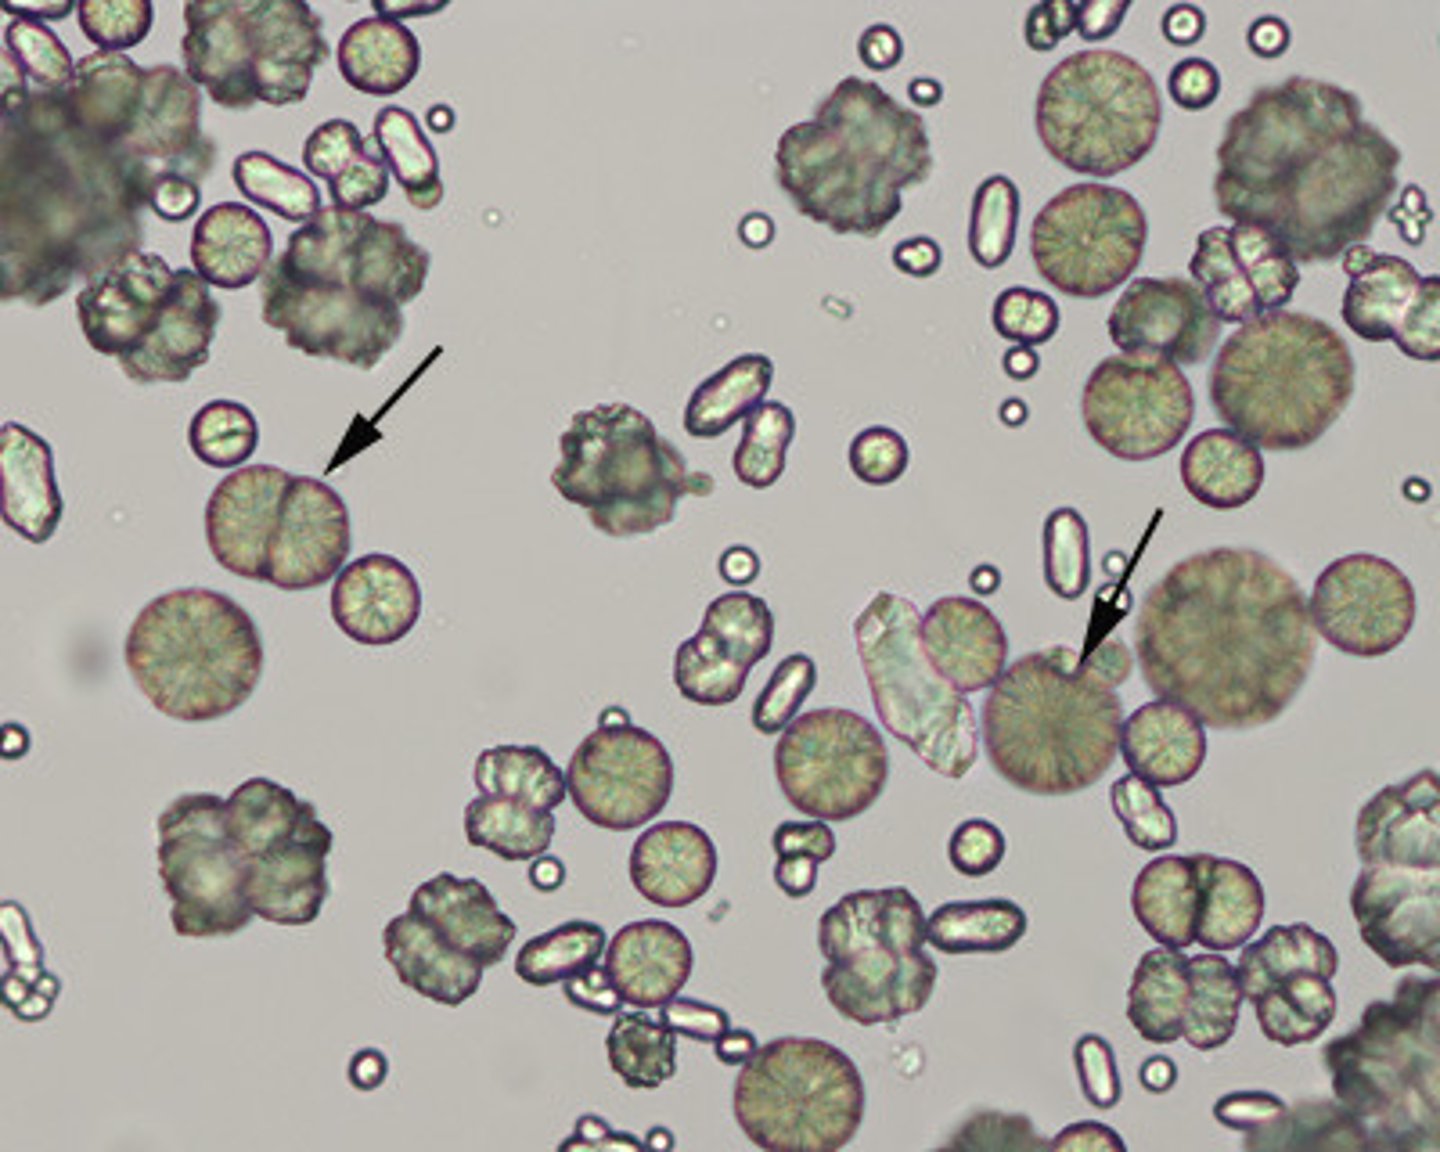

struvite crystals

AKA triple phosphate crystals

urine

colorless, coffin-like prisms/envelope shape

**common